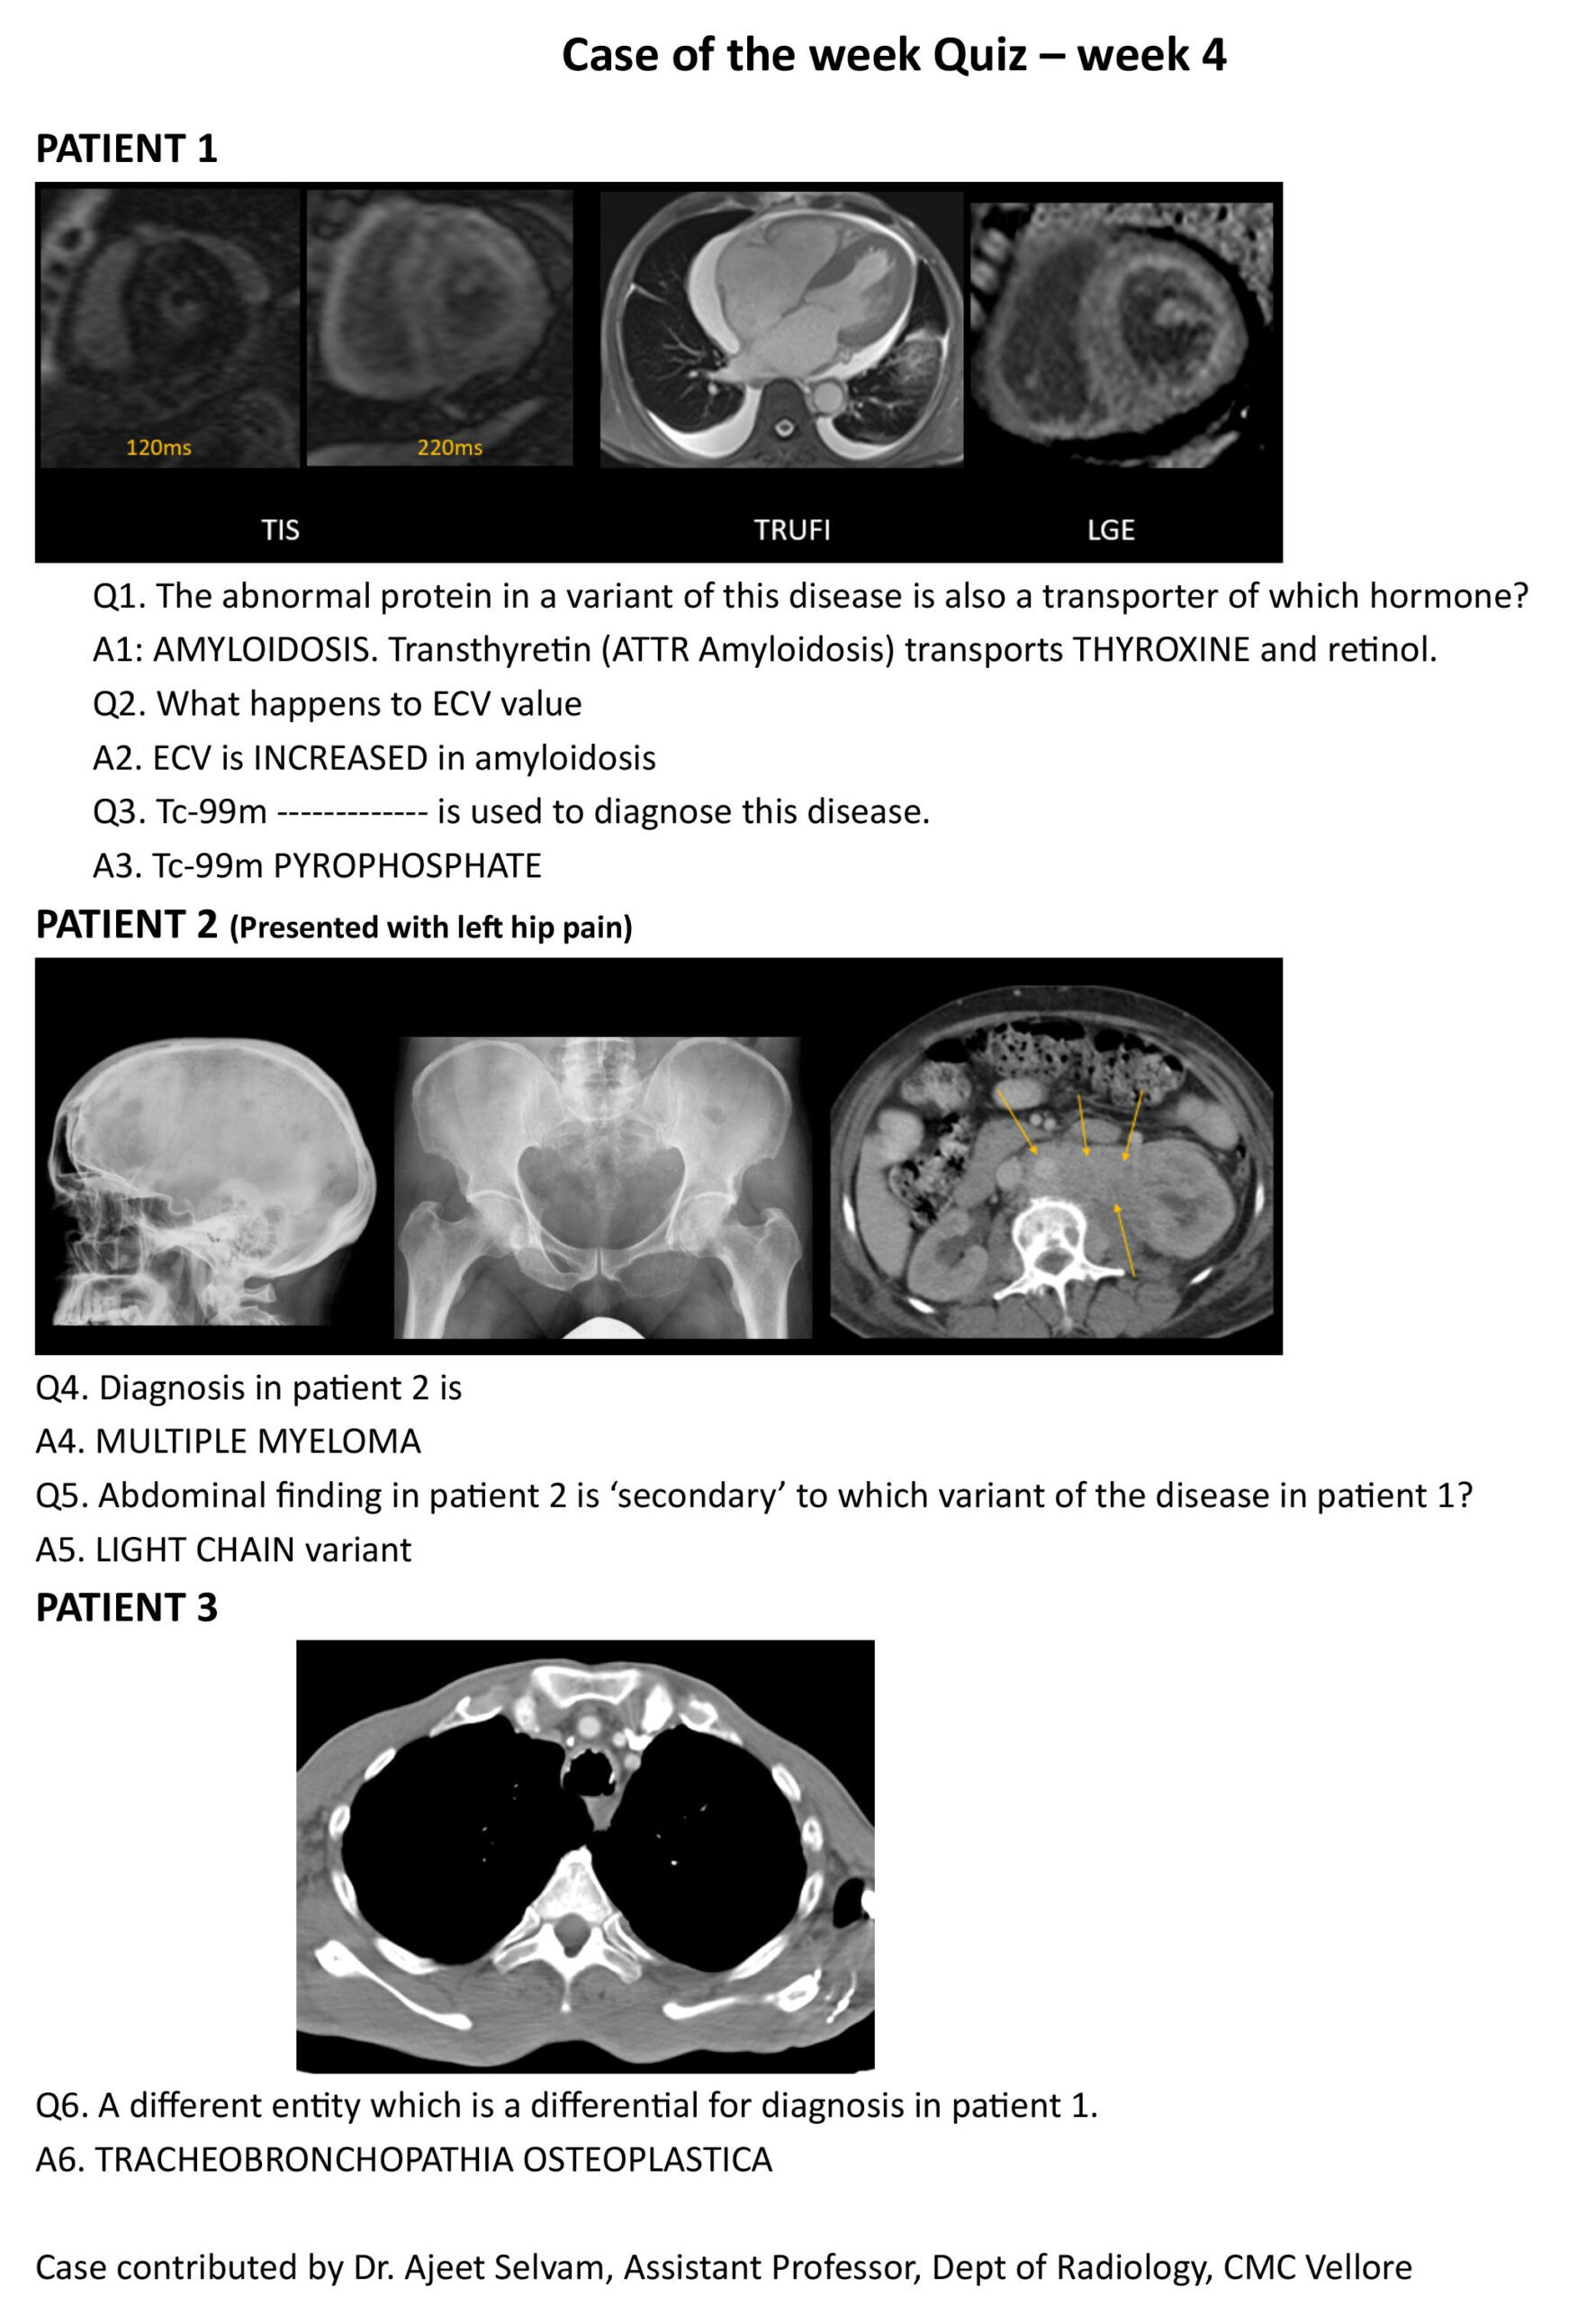

Case of the week Answer Key